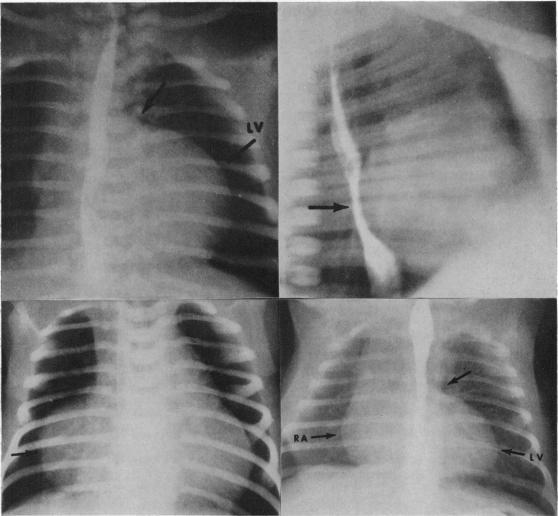

RADIOLOGICAL ASPECTS OF PULMONARY ATRESIA WITH INTACT VENTRICULAR SEPTUM.

Br Heart J. 1963 Sep;25(5):655-62. doi: 10.1136/hrt.25.5.655.